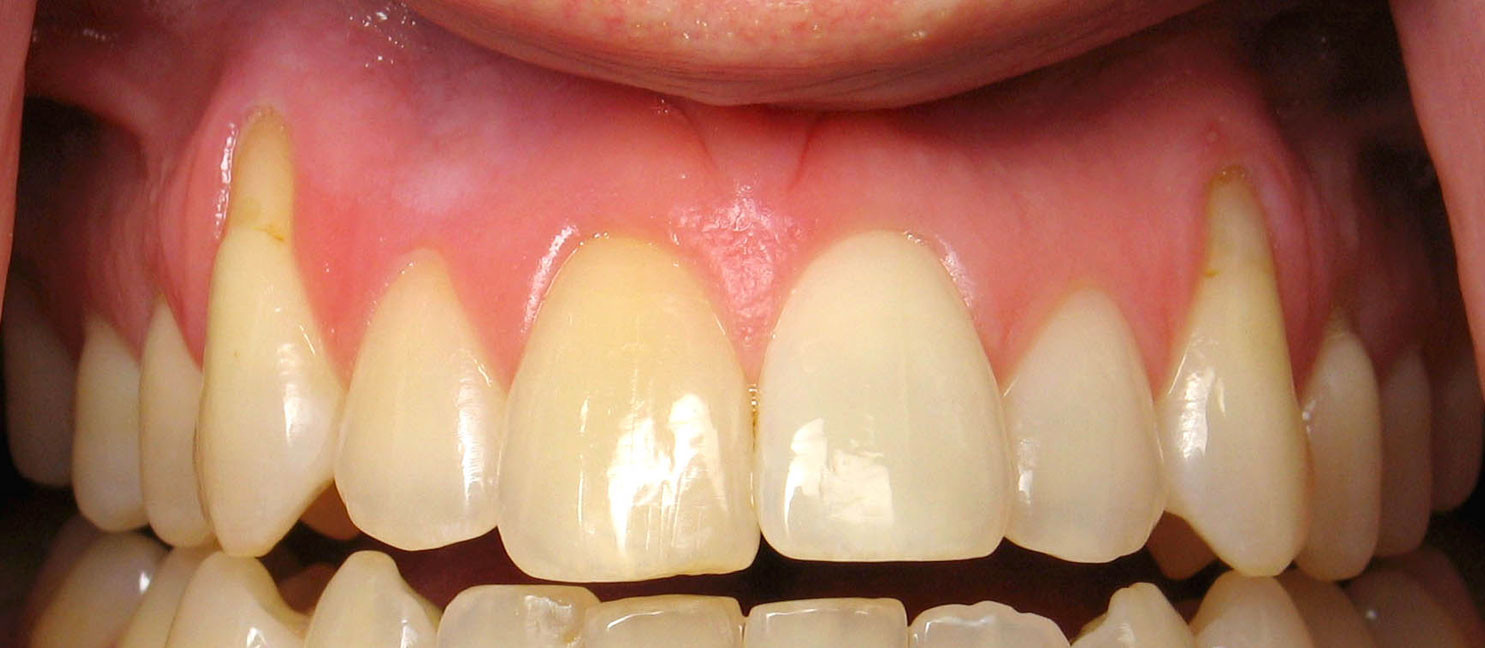

Receding Gums, Symptoms, Causes and Treatment

Gum recession is when the margin of the gum tissue surrounding the teeth wears away, or pulls back, exposing more of the tooth, or the tooth's root. When gums recede, gaps can form between the gum and tooth, allowing disease-causing bacteria to build up. If left untreated, the surrounding tissue and bone structures of the teeth can be damaged.

Receding gums is a widespread dental condition. Most people aren’t aware that they have receding gums since it occurs gradually.

Long Teeth.- One symptom is the visible lengthening of the teeth. When gums recede because of periodontal disease, the teeth have the appearance of being much longer than normal.

Exposed Roots.- Exposed roots are another symptom, and can be extremely sensitive and uncomfortable. They are often a sign of periodontal disease or can be attributed to brushing overly aggressively with a toothbrush with hard bristles.